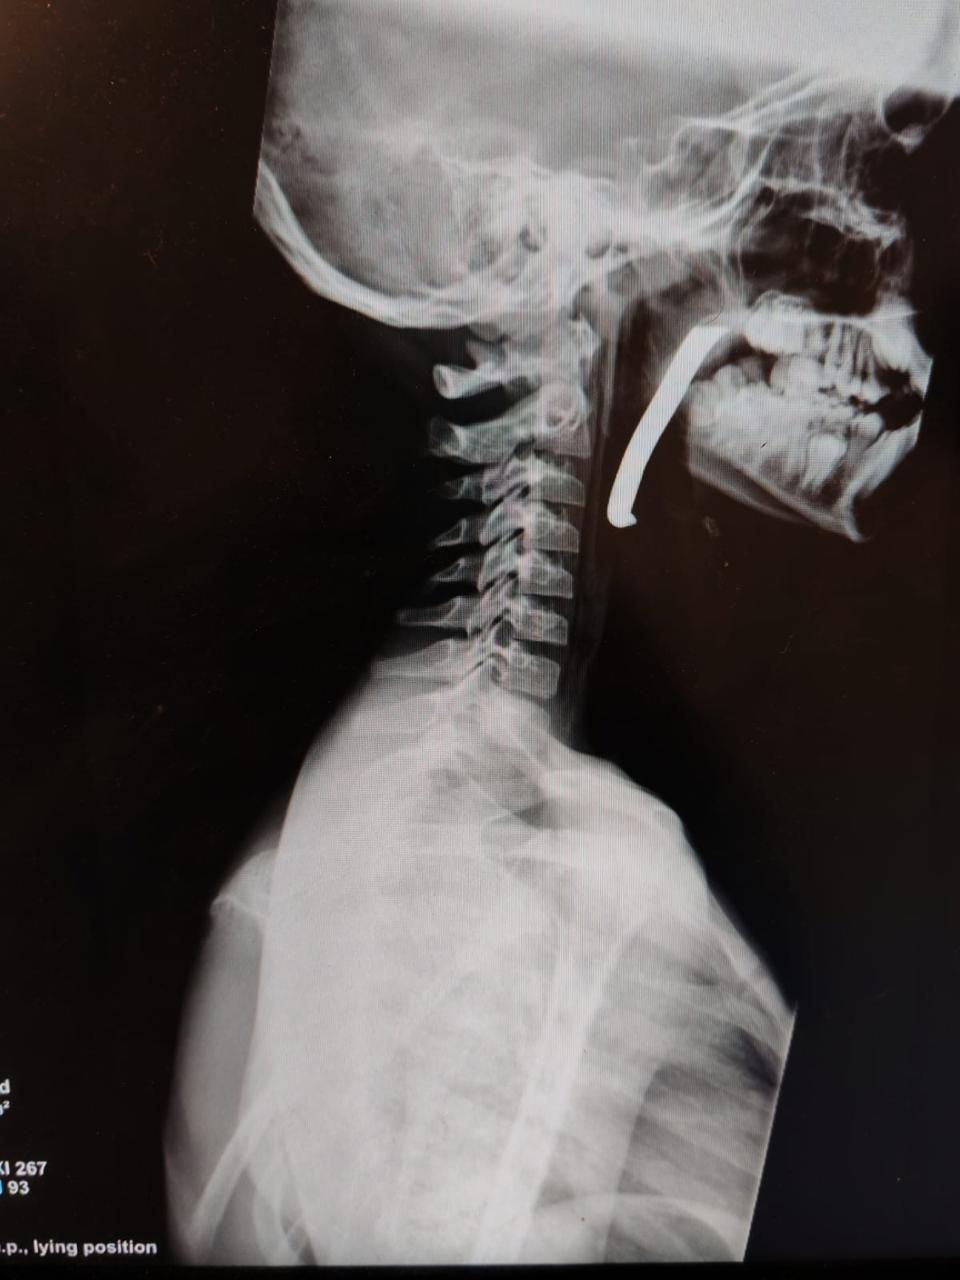

مدار الساعة -أجرت طواقم المستشفى الميداني الأردني جنوب غزة/6، أمس الأحد، عملية جراحية ناجحة لإنقاذ حياة طفل، تم خلالها استخراج شظية كبيرة الحجم اخترقت الرقبة والبلعوم والمجرى التنفسي، وذلك من خلال استكشاف جراحي دقيق للرقبة.

وأوضح مدير المستشفى أن الطفل كان يعاني من إصابة بالغة على مستوى الرقبة والبلعوم، حيث اخترقت الشظية مناطق حيوية وأدت إلى صعوبة في التنفس، مما شكل تهديداً مباشراً لحياته. وأضاف أن الحالة كانت حرجة، وتطلبت تدخلاً جراحياً فورياً نفذه فريق طبي متخصص يضم أطباء في الجراحة العامة، والتخدير والإنعاش، وجراحة الأطفال، وجراحة الأنف والأذن والحنجرة، وبمتابعة دقيقة من الأطباء المختصين، وتم استخراج الشظية بنجاح عن طريق الفم، وحالة الطفل الآن مستقرة.